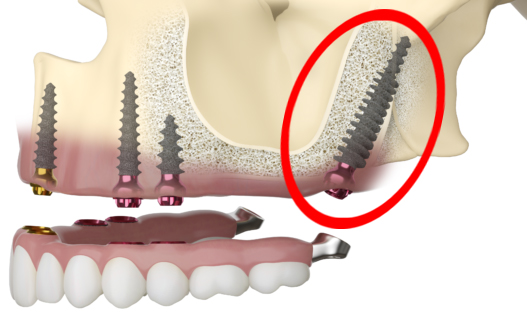

Pterygoid Implants can play a crucial role in the All-On-4 procedure, especially in cases where patients have severe bone loss in the posterior upper jaw. While the standard All-On-4 procedure relies on angling the posterior implants to maximize the use of available bone, there may still be situations where the bone volume is not sufficient for secure implant placement.

In these cases, Pterygoid Implants can provide an effective solution. Their longer length and unique placement in the pterygoid plates of the sphenoid bone allow them to harness support from the denser bone in this region, thus overcoming the challenge of insufficient bone volume.

Incorporating Pterygoid Implants into the All-On-4 protocol can enhance the stability and durability of the prosthesis, particularly in the posterior region. This combination approach allows for a wider spread of force during chewing, creating a more natural and comfortable experience for the patient. It also reduces the risk of prosthetic failure due to overloading of the anterior implants, ensuring a long-lasting and successful outcome.

Eliminating Cantilever with Pterygoid Implants

A significant advantage of incorporating Pterygoid Implants into the All-On-4 protocol is the elimination of cantilevers. In the standard All-On-4 design, the posterior teeth are not directly supported by implants but are extended beyond the posterior-most implants, forming a cantilever. While this design is generally effective, it can cause excessive force on the anterior implants when chewing hard or sticky foods, potentially leading to complications over time.

With the addition of Pterygoid Implants, these posterior teeth can be directly supported by implants, effectively eliminating the cantilever. This not only improves the distribution of chewing forces but also enhances the stability and strength of the overall prosthesis.

By reducing the strain on the anterior implants, the risk of implant failure is minimized. Furthermore, the elimination of the cantilever allows for a better reproduction of natural tooth function, offering a more comfortable and natural feel for patients. Ultimately, the incorporation of Pterygoid Implants into the All-On-4 procedure results in a more robust and durable full-mouth rehabilitation solution.